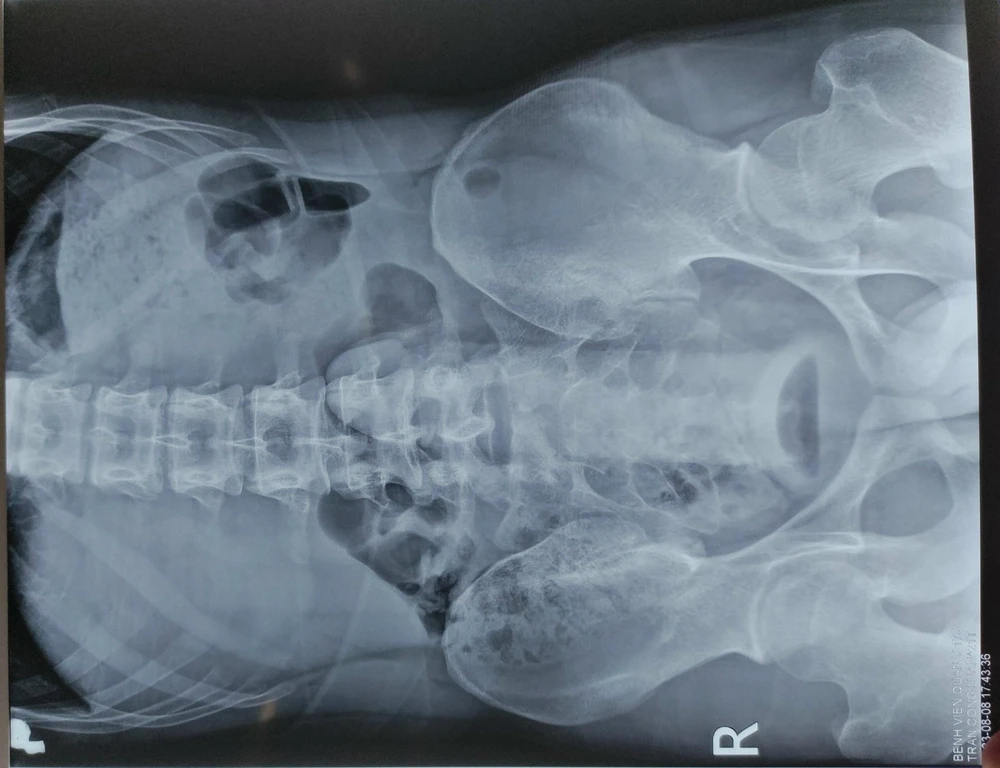

Bệnh nhân được đưa đến khoa Cấp cứu (BV Quân y 175). Sau khi thăm khám và chụp X-quang, các BS phát hiện trực tràng có dị vật hình dạng giống dương vật nằm sâu trong trực tràng. Bệnh nhân được chuyển lên khoa Phẫu thuật - gây mê hồi sức tiến hành lấy dị vật.

| Qua phim X-quang, bác sĩ phát hiện dị vật đã chui sâu vào trong trực tràng của nam bệnh nhân. Ảnh: BVCC |